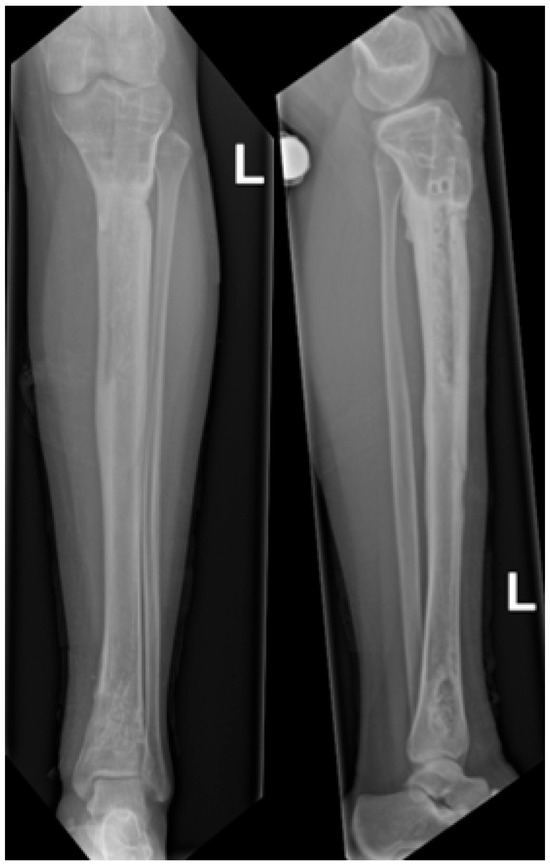

Background: Reconstructing large bone defects in pediatric patients after tumor resection is challenging, as conventional techniques are associated with high complication rates and morbidity. The Intramedullary Bone Transport Nail (IMBTN) may reduce these complications while preserving limb alignment and skeletal growth in pediatric oncologic reconstruction. Methods: A 15-year-old female with an osteofibrous dysplasia-like adamantinoma of the tibial diaphysis underwent complete en-bloc resection, leaving a 9 cm bone defect. An IMBTN (Precice, NuVasive) was implanted for distraction osteogenesis, with distraction starting eight days post-surgery at 0.25 mm twice daily. Follow-up visits monitored bone healing, alignment, and limb length. Results: The 9 cm defect was successfully reconstructed, with complete bone healing at the distraction site. Complete consolidation was confirmed at 18 months. The transport nail was removed at two years, and no further revisions were necessary. At two-year follow-up, the patient reported minimal pain on the Visual Analog Scale 1/10, and no recurrence of the tumor was noted. Conclusions: The use of IMBTN for large bone defect reconstruction following tumor resection in pediatric patients is a safe and effective technique. It enables stable bone transport while preserving alignment, maintaining limb length, and is less invasive than traditional reconstructive approaches. Full article

Figure 1